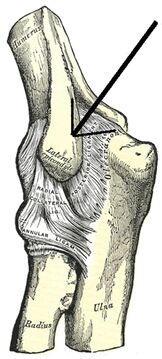

| 13:22, 14. Jan. 2011 | Tennisarm.jpg (Datei) |  |

126 KB | USykora | '''"Innenansicht" eines Ellenbogen'''<br> Bildquelle: commons.wikimedia.org <br> Autor: Gray's Anatomy | 1 |